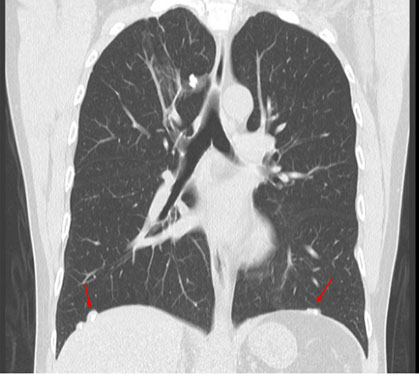

Complementaria: Tomografía computadorizada de tórax de alta resolución. 36 (TCAR), sin contraste: en caso de lectura de radiografía de tórax con técnica OIT que muestre opacidades irregulares de predominio, en bases pulmonares con profusión 1/0 y 1/1. Además, es una herramienta fundamental para la realización de diagnóstico diferencial (Figura 2).

Frente a la presencia de alteraciones pleurales en la Radiografía de tórax con técnica OIT y confirmadas con tomografía computarizada de tórax de alta resolución sin contraste (TCAR), será de vital importancia realizar el diagnóstico diferencial sobre alteraciones pleurales asociadas a la exposición al amianto (Figuras 2, 3, 4 y 5). Entre las patologías diferenciales se incluyen: 53

Radiografía de tórax con técnica OIT: La radiografía de tórax con técnica OIT es una herramienta inicial para evaluar las alteraciones pleurales. Puede revelar la presencia de derrame pleural, engrosamiento o calcificaciones pleurales (Figura 3).